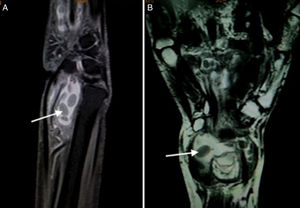

(A) T2W FAT SAT sagittal image show a well defined fluid intensity collection seen along the flexor tendon sheath with presence of hypointense layered rice grain (white arrow) shaped within it suggestive of tenosynovitis with multiple loose bodies. (B) T2W Coronal images show well defined fluid intensity collection anterior to the wrist joint along the flexor tendon sheath suggestive of tenosynovitis. Multiple layered hypointense loose bodies like rice grain are seen within it (arrow).

A 50-year-old lady came with progressive pain and isolated swelling of the right wrist of 9 months duration. Physical examination revealed an oblong swelling on the volar aspect of wrist extending into the forearm. Attempted active flexion at the wrist was painful though passive range of movement was normal. Laboratory investigations showed raised erythrocyte sedimentation rate of 50mm/h. Radiograph of the wrist was normal. MRI revealed well-defined fluid intensity collection along the flexor tendon sheath with presence of hypointense-layered lucencies within suggestive of tenosynovitis with rice bodies (Fig. 1A and B). The adjacent bone and soft tissues were normal. Fluid obtained by ultrasound-guided aspiration from the tenosynovial swelling was positive for Acid Fast Bacilli. Culture grew Mycobacterium Tuberculosis and hence, diagnosis of tuberculosis was reached. The patient did not have diabetes and was not on any immunosuppressive drugs. Serology for Human Immunodeficiency Virus (HIV) was non-reactive. The patient responded to six months of anti-tuberculous therapy with complete resolution of pain and swelling.